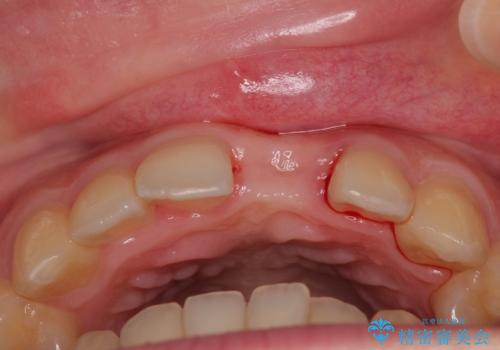

- 前歯のインプラント治療を希望して来院された患者様です。

小学生の時に前歯を殴打したとのことで、歯根が吸収してしまい、抜歯が必要と判断されました。

抜歯、インプラント埋入、仮歯の装着が同時に可能な1DAYインプラントを行いたいところでしたが、吸収による歯肉の炎症が著しいため、抜歯後に炎症が治まるまで待機し、極力早期にインプラント埋入を行うこととしました。